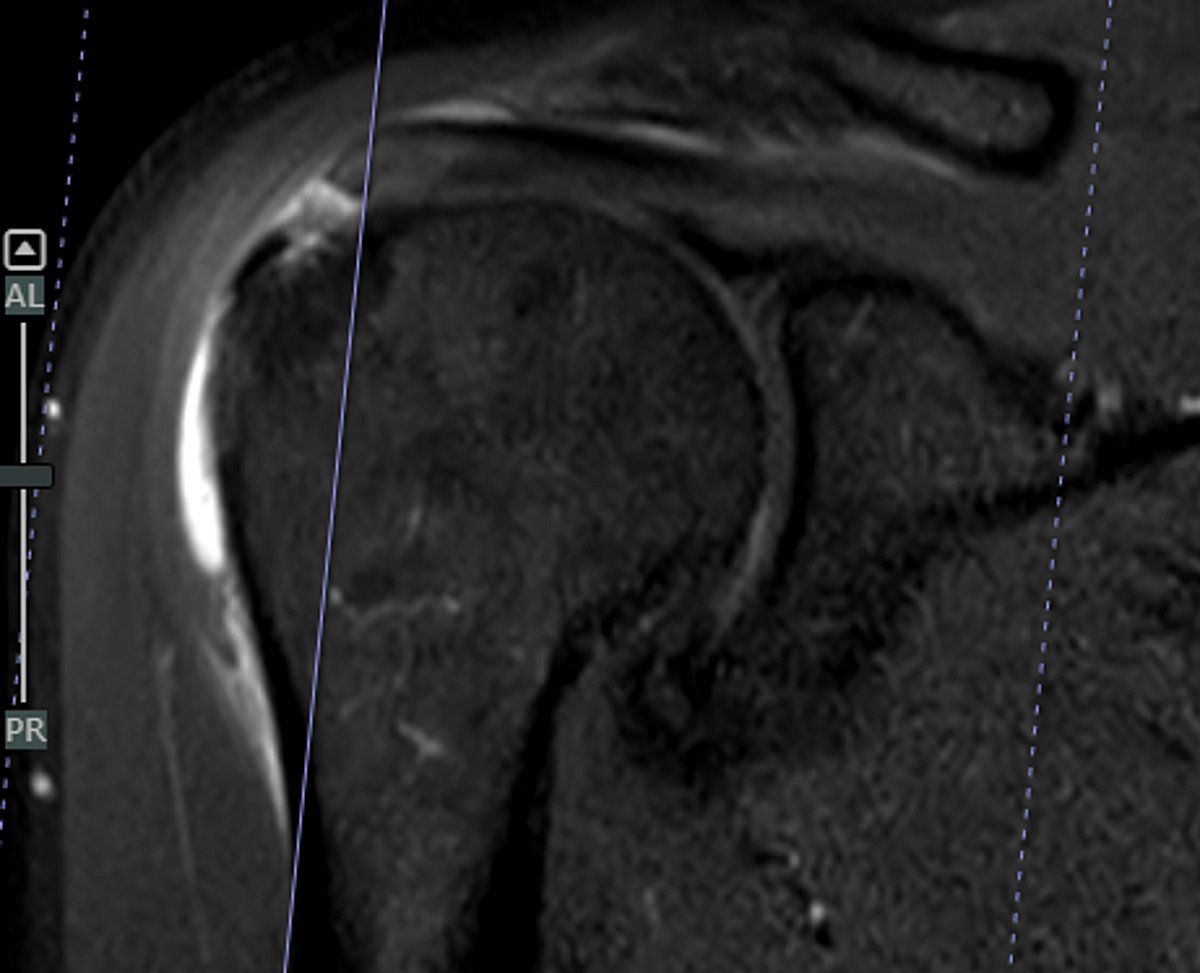

حقق قسم جراحة العظام في مستشفى المانع – فرع الخبر إنجازًا طبيًا لافتًا، بقيادة الدكتور محمد المجتبى ، بعد أن تمكن مريض يبلغ من العمر 61 عامًا من استعادة كامل مدى الحركة في كتفه خلال أربعة أسابيع فقط من خضوعه لعملية إصلاح الأوتار بالمنظار باستخدام رقعة الكولاجين التعويضية، وهي تقنية طبية حديثة تُستخدم لتعزيز التئام الأوتار وتسريع عملية التعافي.

وخضع المريض عقب العملية لبرنامج تأهيلي متكامل داخل مركز التأهيل الرياضي التابع لفرع الخبر، حيث عبّر عن امتنانه للدكتور محمد مجتبا والفريق الطبي وللمستشفى، مؤكدًا أن هذا الإجراء المتطور أحدث فرقًا حقيقيًا في جودة حياته وعودته السريعة لممارسة نشاطه اليومي.

وتُعد هذه النتيجة استثنائية مقارنة بالعمليات التقليدية لإصلاح الأوتار، والتي قد يستغرق التعافي الكامل بعدها ما يصل إلى ستة أشهر، في حين تمكن المريض في هذه الحالة من العودة إلى حياته الطبيعية دون آلام أو ضعف خلال شهر واحد فقط.

كما أبدى المريض استعداده لمشاركة تجربته عبر أو شهادة مكتوبة بهدف إلهام المرضى الآخرين، خاصة مع توفر توثيق مرئي للعملية ومراحل التعافي، مما يعكس مستوى الرعاية الطبية المتقدمة والخبرة التخصصية التي يقدمها قسم جراحة العظام في مستشفيات المانع – فرع الخبر.